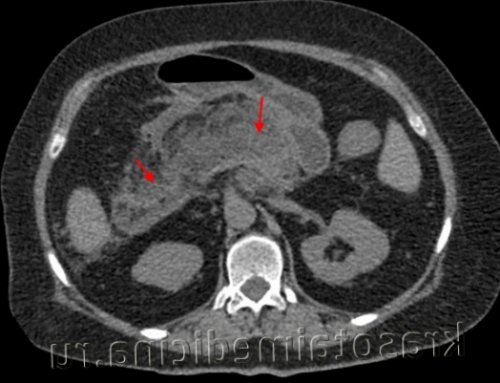

Муковисцидоз

• КТ (компьютерная томография) и МРТ (магнитно-резонансная томография) поджелудочной железы;Диагностика острого панкреатита• злоупотребление алкоголем;Панкреатит может быть инфекционного и неинфекционного происхождения. Вирусный панкреатит возникает вследствие инфекционного поражения поджелудочной железы, например, при кори, вирусном гепатите, туберкулезе.• вздутие живота, тяжесть;• тошнота и рвота, в рвотных массах иногда присутствует желчь;Острый панкреатит — это воспаление тканей поджелудочной железы, одним из главных признаков которого является острая боль в животе 1 . Это достаточно тяжелое заболевание, которое требует обращения к врачу и безотлагательного лечения.При тяжелой форме применяют октапептиды, селективно угнетающие панкреатическую секрецию, проводят интенсивную терапию для поддержания АД, стабилизации метаболических нарушений. Пациентам с установленной этиологией панкреатита показано лечение основного заболевания. При остром панкреонекрозе может выполняться некрэктомия поджелудочной железы, оментобурсостомия. При стойких болях, связанных с наличием кистозных образований, производится удаление ложных кист поджелудочной железы или марсупиализация истинных кист.• Обезболивающие препараты. Обычно используют ненаркотические анальгетики, которые при наличии спастических дискинезий дополняют миотропными спазмолитиками. При интенсивном болевом синдроме показана эпидуральная блокада, введение наркотиков.КТ органов брюшной полости. Панкреатит (в области хвоста поджелудочной железы) с наличием отека ее паренхимы, жидкостного содержимого вблизи ее края, на фоне утолщение фасции Героты слева• Исследование панкреатических ферментов в крови. Повышение уровня альфа-амилазы в 3-4 раза (при норме до 50 Ед/л) в первые сутки указывает на острый процесс или обострение хронического воспаления. С 4 суток проводят измерение уровня липазы — диагностически значимо двукратное увеличение показателя.Классическими симптомами острого панкреатита является триада Мондора — вздутие живота, сильная, внезапная боль, которая может привести к потере сознания, и многократная рвота, не приносящая облегчения. Кроме того, общее состояние пациента обычно быстро ухудшается с такими отличительными признаками, как тахикардия, снижение артериального давления, повышенная потливость и бледность кожи.• Особенности клинического течения. Хронический панкреатит бывает редко и часто рецидивирующим. При постоянном наличии симптоматики говорят о персистирующем течении заболевания.